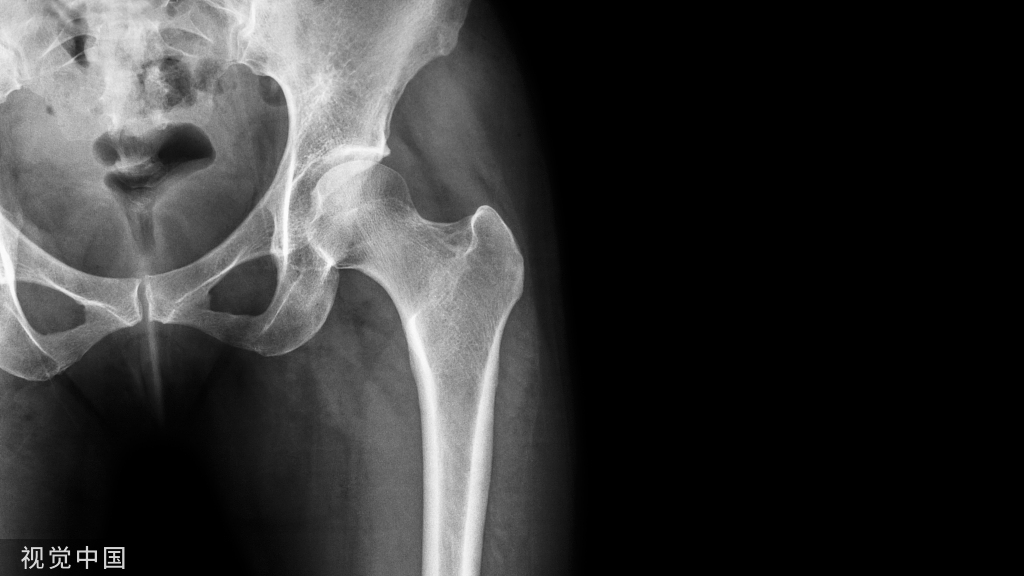

术后x光片显示髋臼陶瓷内衬骨折